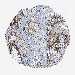

Basal cell and squamous cell cancer

SKIN CANCER - Protein expressioni

A mouse-over function shows sample information and annotation data. Click on an image to view it in a full screen mode. Samples can be filtered based on level of antibody staining by selecting one or several of the following categories: high, medium, low and not detected. The assay and annotation is described here.

Each image is clickable and will lead to virtual microscopy that enables deeper exploration of all samples and also displays staining intensity scores, fraction scores and subcellular localization as well as patient and tissue information for each sample.

Antibody HPA029619

Antibody HPA029621

Staining

High

Medium

Low

Not detected

Intensity

Strong

Moderate

Weak

Negative

Quantity

>75%

75%-25%

<25%

None

Location

Nuclear

Cytoplasmic/membranous

Cytoplasmic/membranous,nuclear

Basal cell carcinoma

Squamous cell carcinoma, NOS

Squamous cell carcinoma, metastatic, NOS